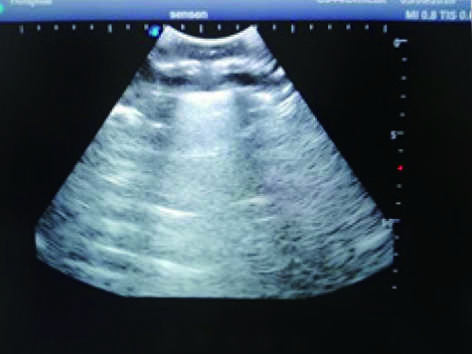

This model is an ideal choice for ultrasound-guided thoracentesis training with true-to-life skin feel and touch, accurate anatomical structures as well as real clinical ultrasound images. Realistic resistance to needle tips and correct landmarks provide excellent hands-on experience.

2)  Real clinical ultrasound images with clear muscles, connective tissues, lungs and pleural structures